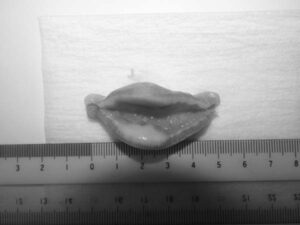

ワンちゃんが乳腺にできた複数のシコリを気にされて来院されました。bilateral mastectomyで対応しました。摘出後の病理組織検査の結果は、「R3-4間腫瘤:乳腺癌(複合型)」でそれ以外は「良性乳腺混合腫瘍」でした。無事元気に退院し、その後再発もなく経過は良好です。よかったね。